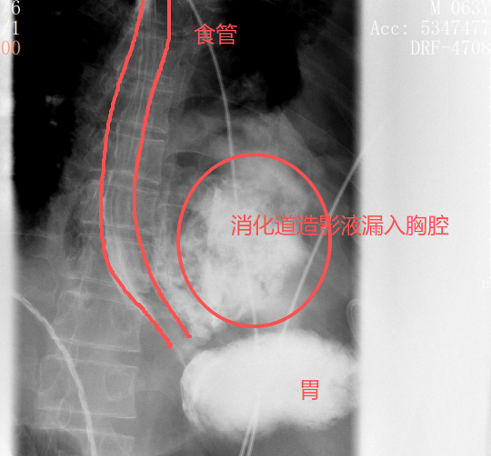

转院时,患者病因成谜。在晨会接班时,胸外科主任刘继先锐利地捕捉到一个要道细节,他多问了一句:“这个病东谈主,股票配资系统发病前有莫得吐逆?”“有!吃完包子之后吐了两次,吐完就初始痛了。”在获取细目复兴后,刘主任立即警醒,判断这可能是一种极为不吉的疾病——“自觉性食管闹翻”(Boerhaave抽象征),并首要安排了口服钡餐检讨。

适度阐明了他的判断:

钡剂从食谈下段的裂口处

多数漏入了左侧胸腔